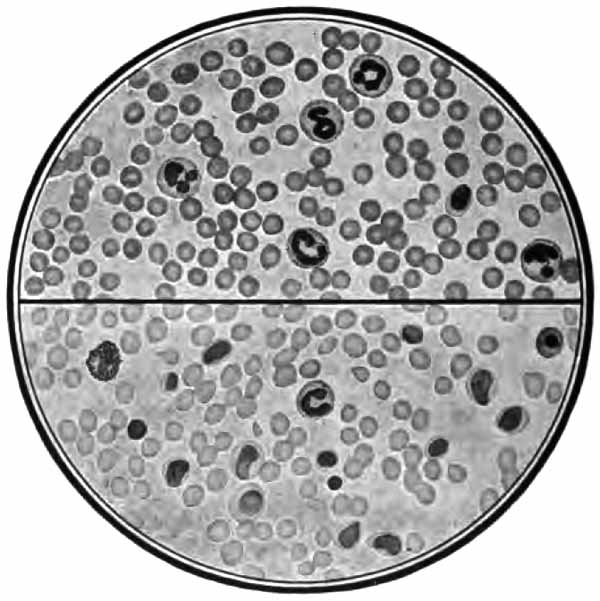

PLATE II

Heart-failure cells in sputum

FIG. 1.—Heart-failure cells in sputum, containing blood-pigment, from a case of cardiac congestion of the lungs (Jakob).

Sputum showing tubercle bacilli

FIG. 2.—A, Sputum showing tubercle bacilli stained with carbol-fuchsin and Gabbet's methylene-blue solution (obj. one-twelfth oil-immersion); B, sputum of anthracosis, showing particles of coal-dust stained with methylene-blue (obj. one-twelfth oil-immersion) (Boston).